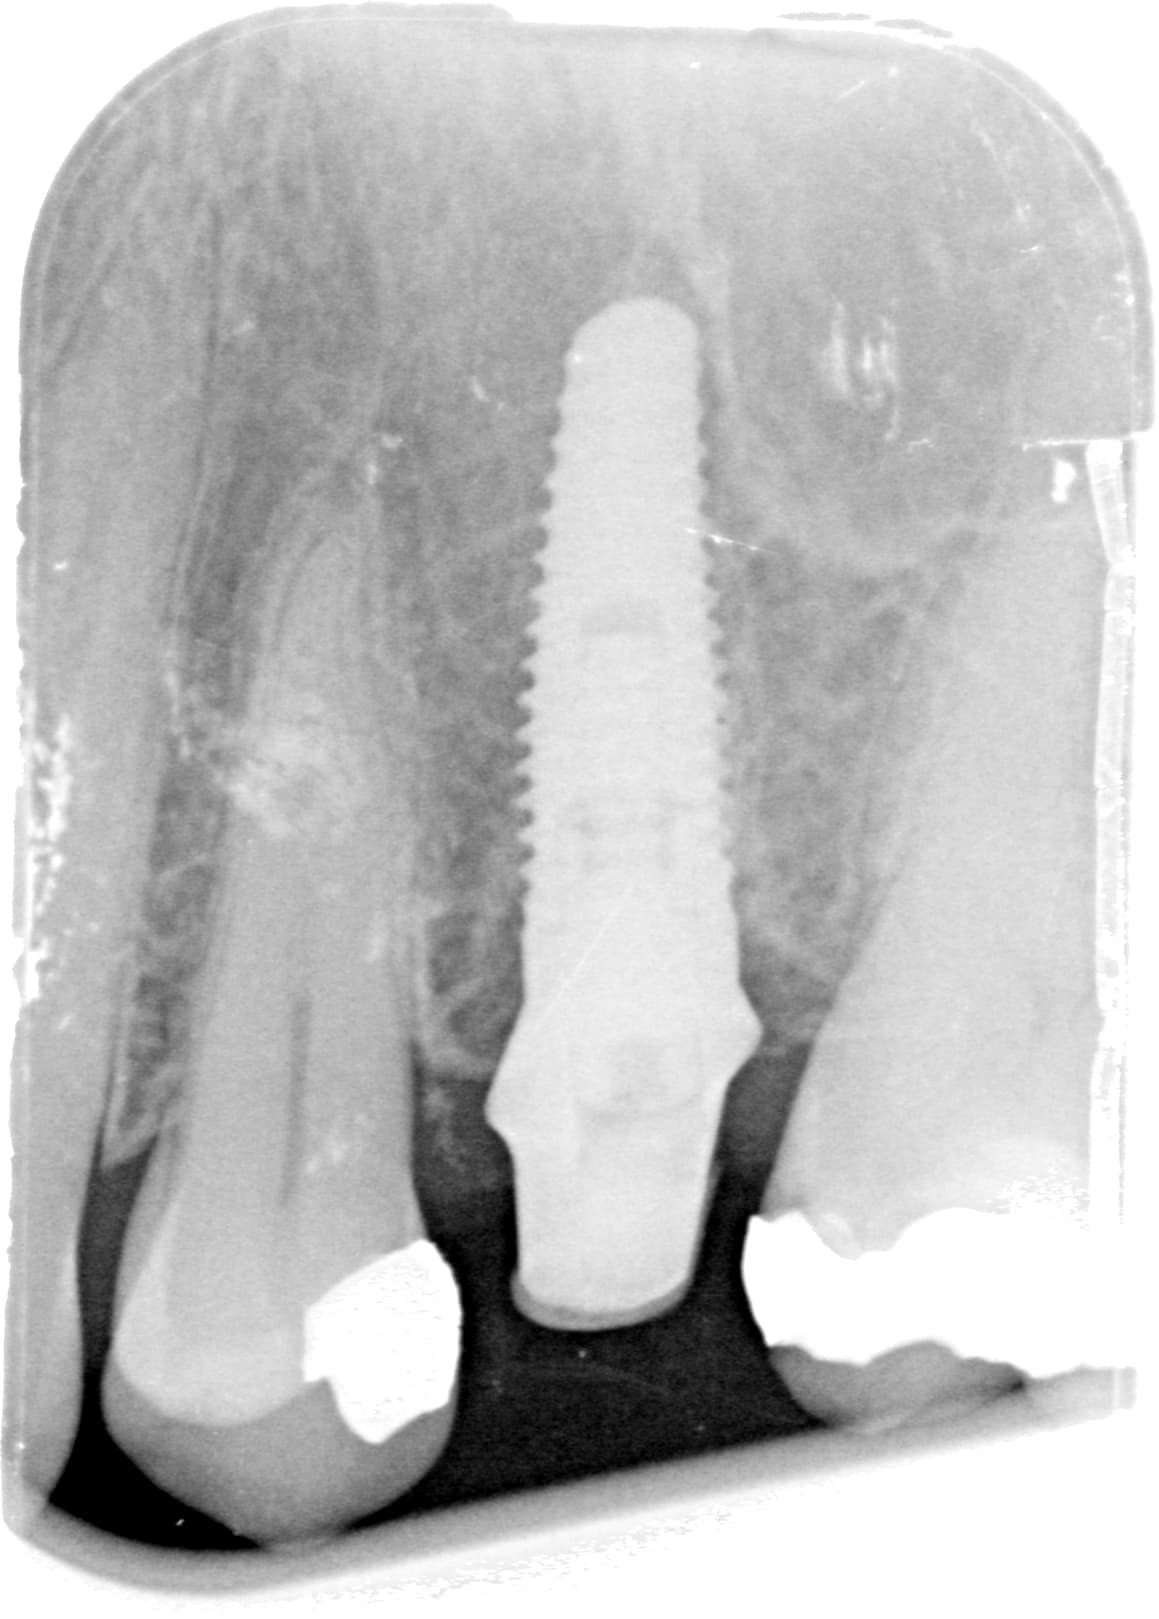

J'ai une patiente avec un implant en 25 posé en Andorre.

La couronne s'est fracturée.

Quel est la référence de cet implant?

Dommage que le contraste soit pas meilleur…..pour mieux distinguer le type de connexion….

Mais il a une bonne tête de Nobel replace